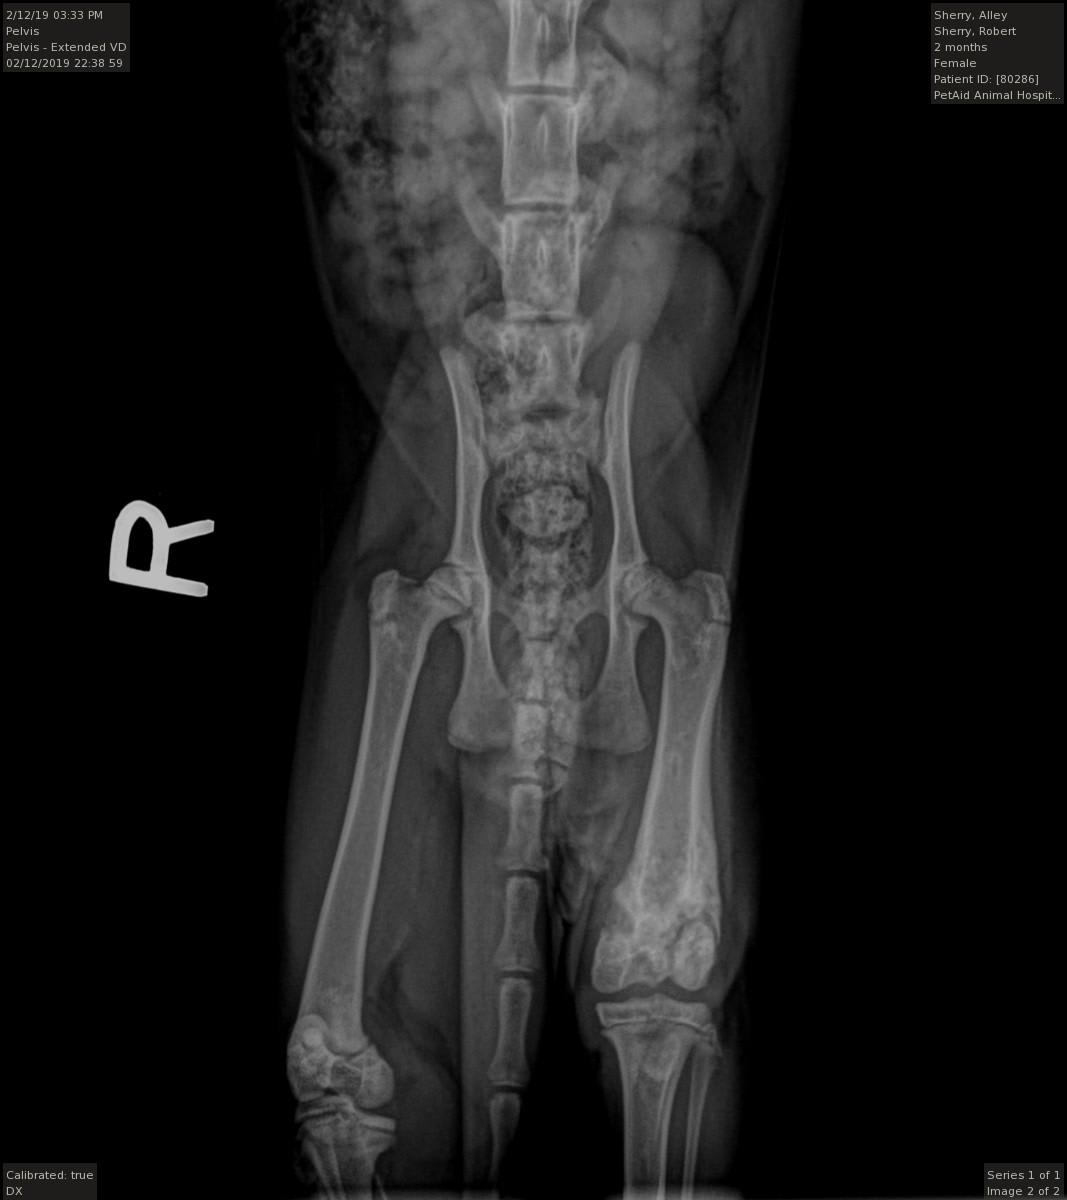

I rescued a young cat (aprox 4 months old) that had a bad limp while walking. Upon taking her to the Vet I discovered that she had her back left leg broken badly while very young and it had never been set (see X-Rays). The vet is recommending amputation. I would like another opinion. She runs, jumps, plays and sleeps on her left side, but limps badly walking. Thank You..